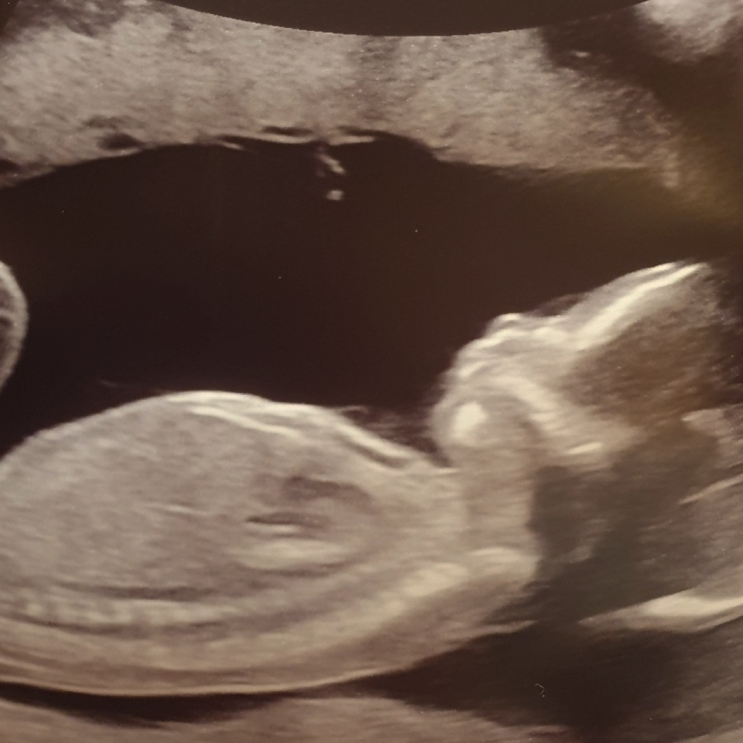

#임신중기 일상(임신 16주/까꿍이 성별은?)

안녕하세요! 또 잠잠하다 임신일기 쓰러 살짝쿵 놀러왔어요:) 벌써 까꿍이는 임신중기 16주 4일차가 되었어...